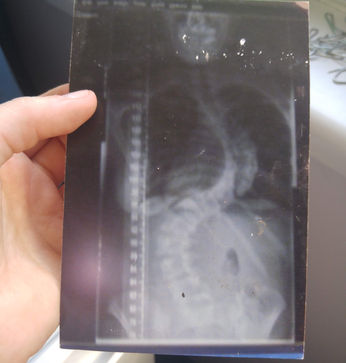

When I was eleven, my ballet teacher gently asked why I was leaning to one side during class. I told her, quite honestly, that I was trying to stand up straight. That simple comment led to a referral to an orthopedic surgeon, where I was diagnosed with idiopathic scoliosis.

At the age of twelve, I underwent spinal fusion surgery—a life-altering experience that marked the beginning of my journey toward self-acceptance. Navigating recovery during adolescence, a time already filled with emotional and physical changes, was incredibly challenging. Around the same time, I began to struggle with body image and developed an eating disorder.